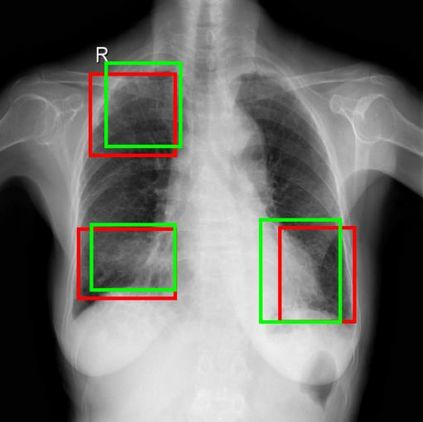

Chest X-ray (CXR) is the most typical diagnostic X-ray examination for screening various thoracic diseases. Automatically localizing lesions from CXR is promising for alleviating radiologists' reading burden. However, CXR datasets are often with massive image-level annotations and scarce lesion-level annotations, and more often, without annotations. Thus far, unifying different supervision granularities to develop thoracic disease detection algorithms has not been comprehensively addressed. In this paper, we present OXnet, the first deep omni-supervised thoracic disease detection network to our best knowledge that uses as much available supervision as possible for CXR diagnosis. We first introduce supervised learning via a one-stage detection model. Then, we inject a global classification head to the detection model and propose dual attention alignment to guide the global gradient to the local detection branch, which enables learning lesion detection from image-level annotations. We also impose intra-class compactness and inter-class separability with global prototype alignment to further enhance the global information learning. Moreover, we leverage a soft focal loss to distill the soft pseudo-labels of unlabeled data generated by a teacher model. Extensive experiments on a large-scale chest X-ray dataset show the proposed OXnet outperforms competitive methods with significant margins. Further, we investigate omni-supervision under various annotation granularities and corroborate OXnet is a promising choice to mitigate the plight of annotation shortage for medical image diagnosis.